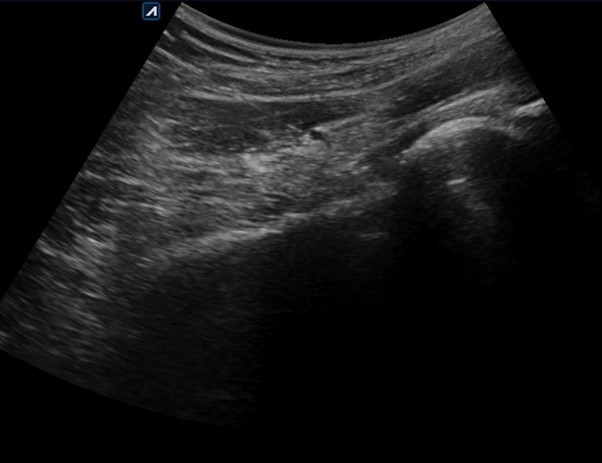

그림6.jpg 촬영 일시: 2025.05.30

<Fig 2. 원인부위에 SI치료하는 영상>

오히려 시술 직후부터

앉았다 일어나는 동작이 한결 편해지셨다고 하셨어요.